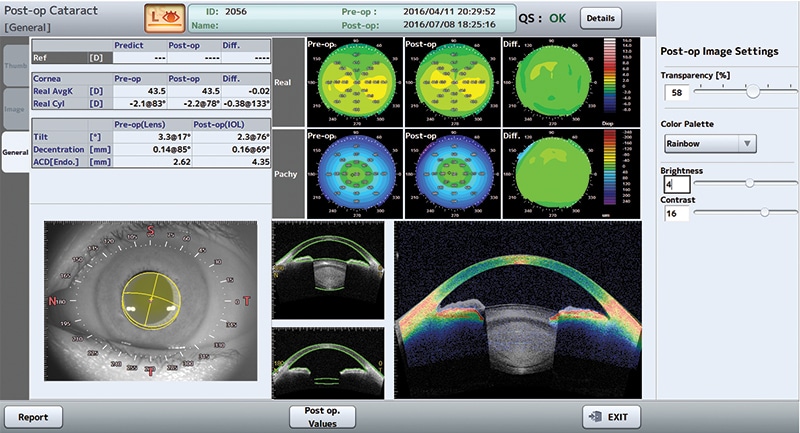

- Testing application for Cataract / Glaucoma / Cornea Surgery

- Corneal topography & IOL choice & calculation

- Lens shape analysis & trend analysis